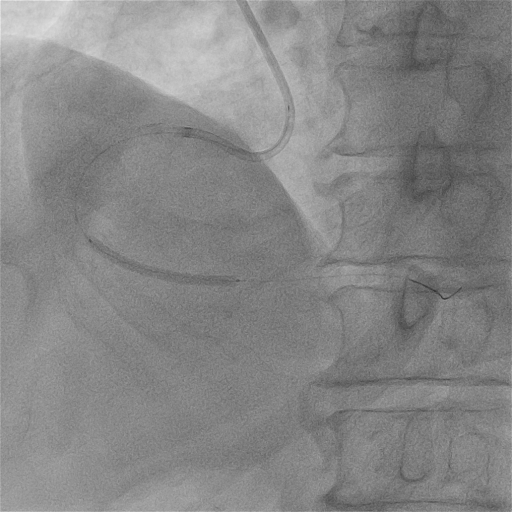

支架植入

于RCA病变处由远及近依次植入2.75*38mm、3.5*38mm、4.0*18mm支架各一枚。

2.75*38mm

3.5*38mm

4.0*18mm

后扩张

用3.0mm、3.5mm及4.0mm高压球囊充分对支架进行后扩张。

最终CAG和IVUS

术后造影及IVUS可见支架膨胀及贴壁良好,支架远近端未见夹层血肿。